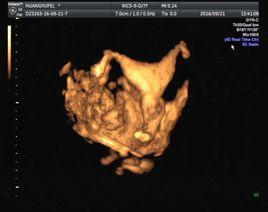

心臟聲學造影技術自上世紀60年代末套用於臨床以來發展很大,右心聲學造影在診斷先天性心臟病方面的價值已得到充分肯定。

將含有微泡的造影劑直接經外周靜脈注入抵達冠脈循環來評價心肌微循環的完整性的心肌灌注聲學造影(MCE)也逐漸進入臨床,由單純定性研究進入定量研究階段。